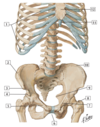

16

Q

13

A

13 - left gastric artery

17

Q

1

A

1 - greater omentum (cut away)

18

Q

2